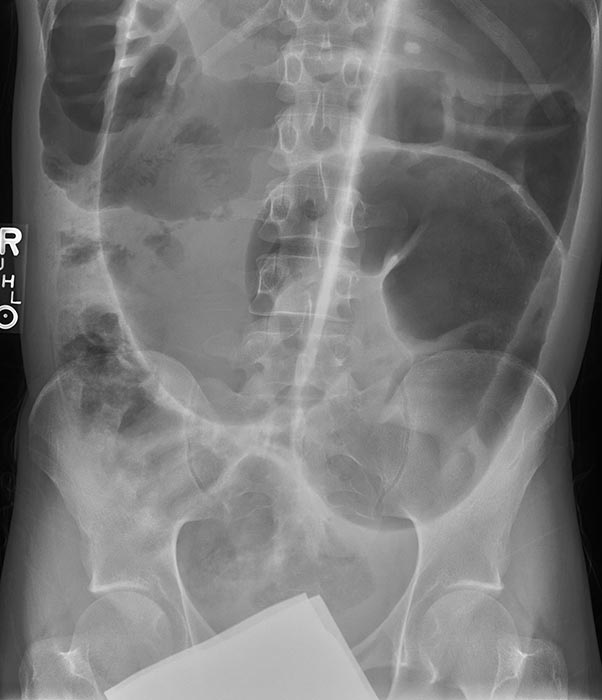

Where does volvulus most commonly occur?

In the cecum and sigmoid colon. (image shows cecal volvulvus)

Which age group commonly experiences sigmoid volvulus?

How does sigmoid volvulus occur?

The sigmoid twists on its mesenteric axis, rotating left or right.